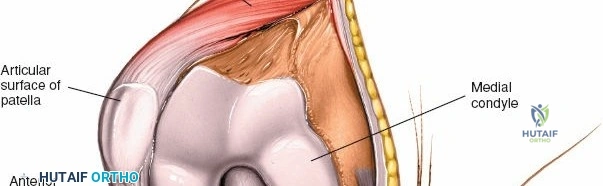

* Patella: The largest sesamoid bone, critical for extensor mechanism efficiency. Its posterior articular surface is covered by hyaline cartilage.

Deep to the extensor mechanism lies the joint capsule, which is continuous with the periosteum of the distal femur and proximal tibia. The capsule forms the suprapatellar pouch proximally, a crucial area for exposure and débridement. The synovial membrane lines the inner surface of the capsule and extends into the joint, forming the intra-articular fat pad (Hoffa's fat pad) distal to the patella.

Once the arthrotomy is complete, the patella is typically everted laterally or subluxated to gain full access to the trochlear groove, femoral condyles, tibial plateau, and menisci.

* Traditional Approach (Patellar Eversion): The patella is gently grasped and everted laterally, typically by flexing the knee to facilitate this maneuver. This provides excellent visualization of all compartments.

Initial stages of patellar eversion, showing retraction of the medial soft tissues and initiation of lateral displacement of the patella.

Further lateral displacement of the patella, demonstrating improved exposure of the trochlear groove and femoral condyle.

Full patellar eversion, offering wide access to the intra-articular structures of the knee, including the femoral condyles and tibial plateau.

- With the patella everted, the suprapatellar pouch is accessible. This is often adherent in osteoarthritic knees and requires sharp dissection to release adhesions and fully visualize the distal femur.